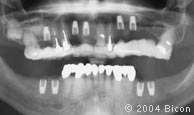

2. |

术前的X光片。 |